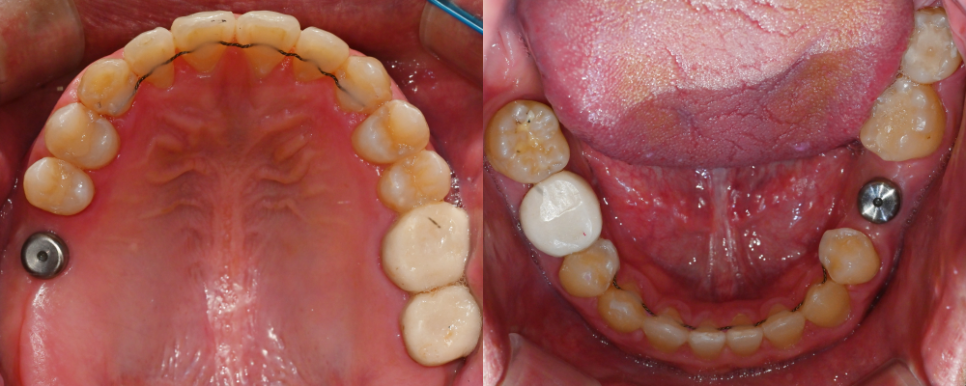

| 임플란트와 교정의 복합 치료 과정

복합적인 치아 문제를 해결하기 위해서는

임플란트와 교정 치료를

체계적으로 조합한 접근이 필요해요.

24.01.10

치아 결손 부위에

임플란트를 식립하기 전에

교정 치료를 먼저 진행하는 경우가 많습니다.

이는 치아 배열을 정리한 후

임플란트를 적절한 위치에

식립하기 위함이에요.

24.08.19//25.01.13

교정 치료 과정에서

반대교합을 동시에 개선하면서

임플란트 식립을 위한 공간을

확보하게 됩니다.

필요에 따라 치간이개를 조절하고

전체적인 치아 배열을 정리해요.

25.04.07

25.04.28

임플란트 식립 시에는 주변 치아와의

조화를 고려해서 위치와 각도를

정밀하게 결정합니다.

25.06.02

최종적으로 보철물을 장착할 때도

전체적인 교합을 고려해서

제작하게 됩니다.